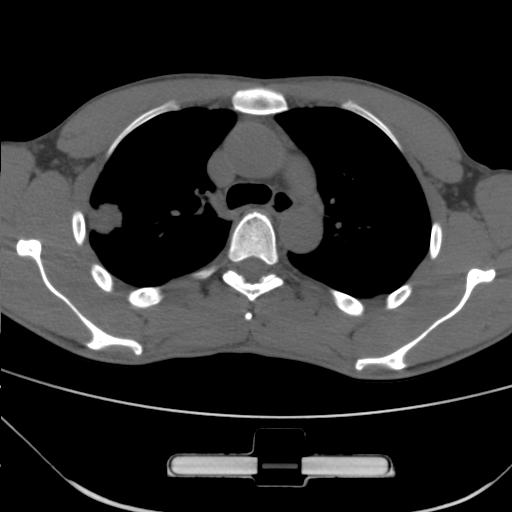

标题: CT25483:肺部病变 请指教

车祸伤者

右肺上叶后段近胸膜下结节样异常密度灶,似见分页及毛刺,考虑右肺上叶周围型肺ca,建议穿刺病理检查

缺乏病史,症状体征,但这个孤立结节具备了几乎所有的恶性征象:分叶,毛刺,空泡征,胸膜凹陷征,血管集束。